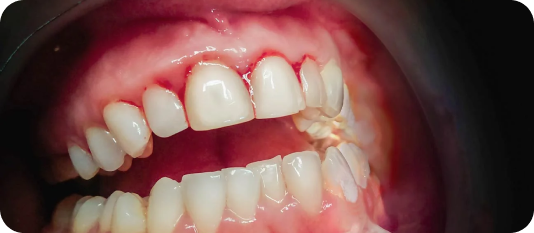

Gums can be treated for diseases leading to tissue infection, bone loss and loose teeth leading to gum disease that can occur when you do not take proper care of your oral health.

Using digital, advanced software, our dental experts will come up with a scientific The surgery can help treat the infected part of the gums by extracting the bacterial formation from under the tissue and sewing it back. This slowly reduces inflammation and prevents further gum disease, improving overall gum health and aesthetics of your facial structure.plan by predicting the result by analysing the tooth movements and deducing the invisible aligners before and after positions.

Take control of your gum health with advanced treatments! Gum surgeries offer effective solutions for gum problems that may not be resolved through non-surgical methods. From gum grafting to periodontal flap surgery, our skilled team will restore your gum health and help you achieve a healthier, more confident smile.